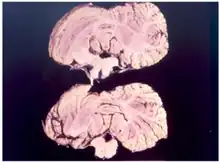

Kuru is a rare, incurable, and fatal neurodegenerative disorder that was formerly common among the Fore people of Papua New Guinea. Kuru is a form of transmissible spongiform encephalopathy (TSE) caused by the transmission of abnormally folded proteins (prions), which leads to symptoms such as tremors and loss of coordination from neurodegeneration.

Kuru, a transmissible spongiform encephalopathy, is a disease of the nervous system that causes physiological and neurological effects which ultimately lead to death. It is characterized by progressive cerebellar ataxia, or loss of coordination and control over muscle movements.[11][12]

In the third and final (terminal) stage, the infected individual's existing symptoms, like ataxia, progress to the point where it is no longer possible to sit up without support. New symptoms also emerge: the individual develops dysphagia, which can lead to severe malnutrition, and may also become incontinent, lose the ability or will to speak, and become unresponsive to their surroundings despite maintaining consciousness.[14] Towards the end of the terminal stage, patients often develop chronic decubitus ulcerated wounds that can be easily infected. An infected person usually dies within three months to two years after the first terminal stage symptoms, often because of aspiration pneumonia[15] or other secondary infections.[16]